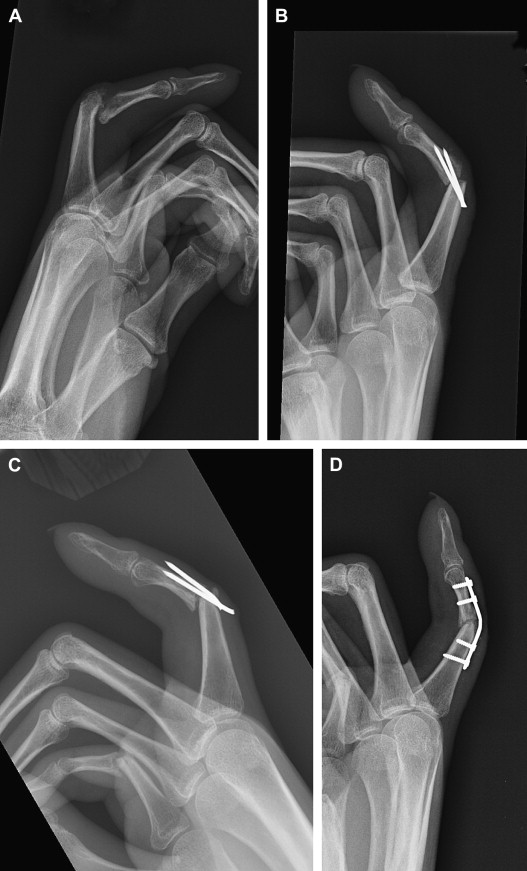

For shaft nonunions, rigid fixation is preferred when there is adequate soft-tissue coverage. The plate size is typically larger than would be used for an acute fracture in the same location. Unfortunately, especially in the phalanges, the soft tissue is often compromised, making plate fixation impossible ( Fig. 3 ). The nonunion site is exposed and nonviable bone is debrided. The void is filled with bone graft and fixation is applied. Early motion is preferred to promote tendon gliding and to minimize adhesions, as these digits are typically stiff from the previous injury.

Amputation should be considered for cases with sensory loss, stiffness, persistent infection, or poor soft-tissue coverage. A stiff digit is often a liability to hand function and, even if the nonunion were to heal, the digit remains stiff and can impair hand function ( Fig. 4 ). Recovery following amputation is often rapid, and leads to improvement in function of the hand.